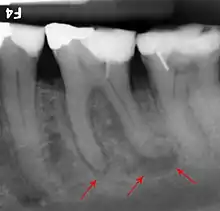

The inferior alveolar nerve (IAN), a branch of the trigeminal nerve (cranial nerve V), is a nerve that runs through the mandible (lower jaw) and supplies sensation to all the lower teeth, the lip and the chin. The lower teeth, and in particular the lower wisdom teeth, can therefore be in close proximity to this nerve. Damage to the inferior alveolar nerve is a risk of lower wisdom tooth removal (and other surgical procedures in the mandible).[17] This means there is a risk of temporary or permanent numbness or altered sensation to the lip +/- chin on the side the surgery is taking place. Therefore, in order to assess this risk and inform the patient, the position of the inferior alveolar nerve in relation to a lower wisdom tooth needs to be assessed radiographically prior to extraction.[17]

The proximity of the root to the canal can be assessed radiographically and there are several factors which can indicate high risk of nerve damage:[18]

- Darkening of the tooth root where it crosses the canal[18]

- Deviation of the canal[18]

- Narrowing of the roots[18]

- Loss of the lamina dura of the canal[18]

- Juxta apical area: a radiolucency associated with the root of the tooth which is not caused by periapical infection[18]